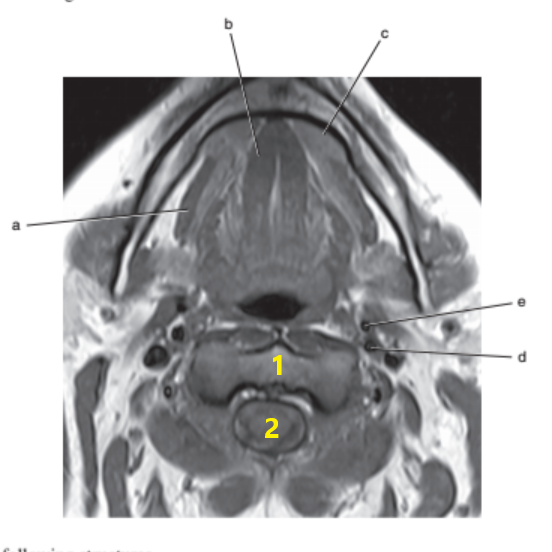

What imaging plane is this ?

transverse

What anatomy is letter b ?

Epiglottis

What is # 1 ?

Tongue

What is # 3 ?

Brain stem

Mandible